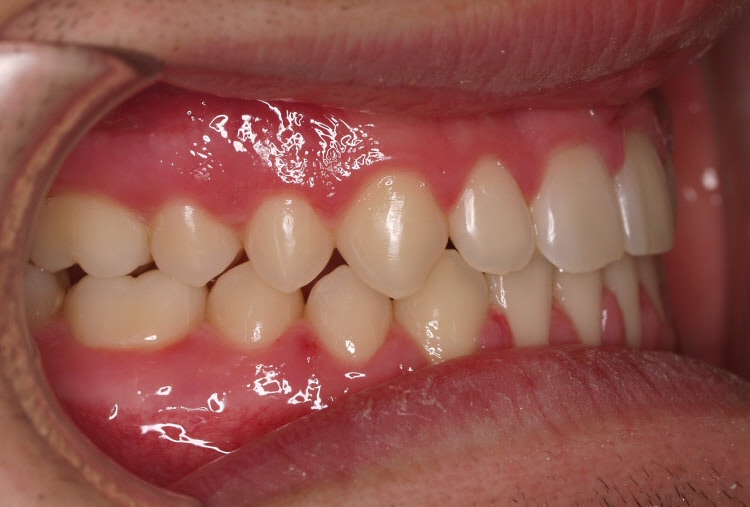

El paciente E.A. acude a nuestra consulta por diastema inferior y ausencia de contactos en los sectores laterales.

1) Arreglamos el problema funcional (lengua baja). Colaboramos con la logopeda Ana Muñoz.

2) Colocamos aparatología fija (brackets Damon) arriba y abajo.